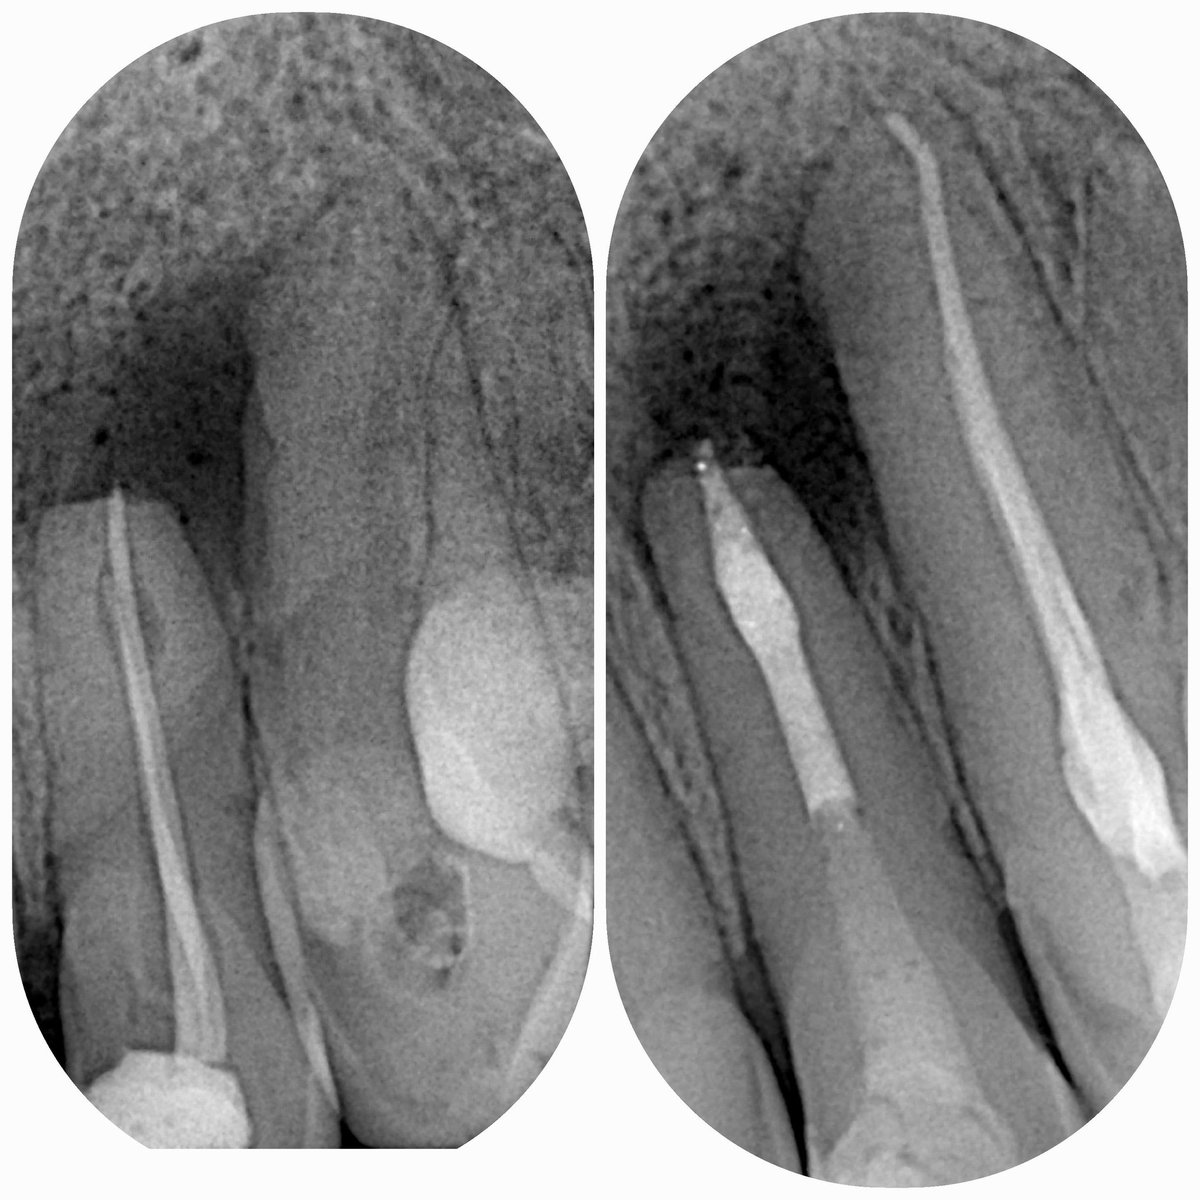

Предсказать реальную глубину процесса сложно, даже по кт. Если полость отчётливо видна уже на рентгене, то ничего хорошего ждать не стоит. Но зуб - это живая единица, и при длительном процессе полость нерва изменяет свою анатомию и "прячется" глубже.

То есть, вырабатывается вторичный дентин, который защищает зуб от процесса. И вроде бы, согласно анатомии, этот самый процесс уже должен был давно вскрыть полость нерва, но нет - иногда оказывается, что это лишь глубокий кариес.

Диагностика кариеса не представляет особой сложности даже для рядового человека. Увидеть темноту на зубе или полость - это просто. А вот различить пигментированную фиссуру от кариеса может только врач, как, и найти кариес между зубами. Так рентген и кт как дополнительные методы.

Зуб 22,значительное воспаление, необычная форма канала, постоянный свищевой ход и болезненность

Удалить боковой резец без попытки реэндо-это точно последнее, что необходимо делать. Имплантация в этой области крайне сложное мероприятие, особенно по розовой эстетике(красивой десне)

Пациенту уже удалили нерв у зуба 23(соседний клык) почему-то доктор решил, что надо срочно спасать этот зуб пока не поздно, не понимаю почему и зачем, но вот срочно, удОооооляем нерв!

А 22 не трогаем, там только удаление.